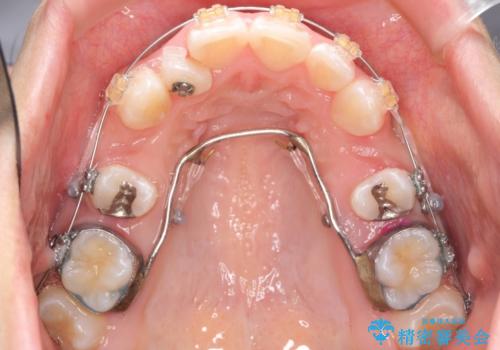

奥歯のかみ合わせもずれていたため、上の奥歯を後ろに下げる処置をミニスクリューを用いて行いました。